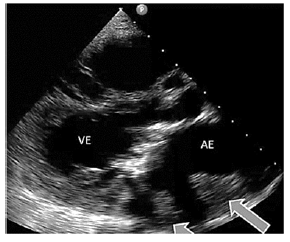

Um paciente de 52 anos de idade, HIV positivo, em ritmo sinusal, apresentou quadro de síndrome coronariana aguda. Ao realizar cateterismo, não havia sinais de doença aterosclerótica. O paciente foi submetido a tromboaspiração. Após o procedimento, foi realizado um ecocardiograma à beira do leito, demonstrado na imagem.

Assinale a alternativa que indica a provável valvopatia associada e o corte ecocardiográfico, respectivamente.